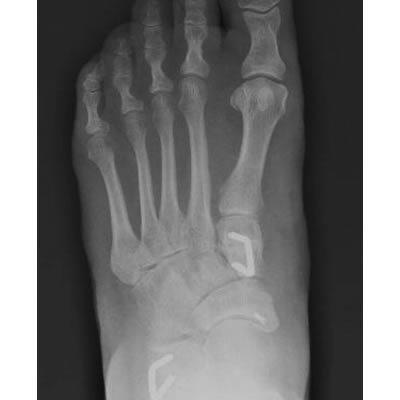

Non Arthritic Flatfoot Deformity

Correction of Deformity with Tendon Augmentation/transfer and Bone Grafting